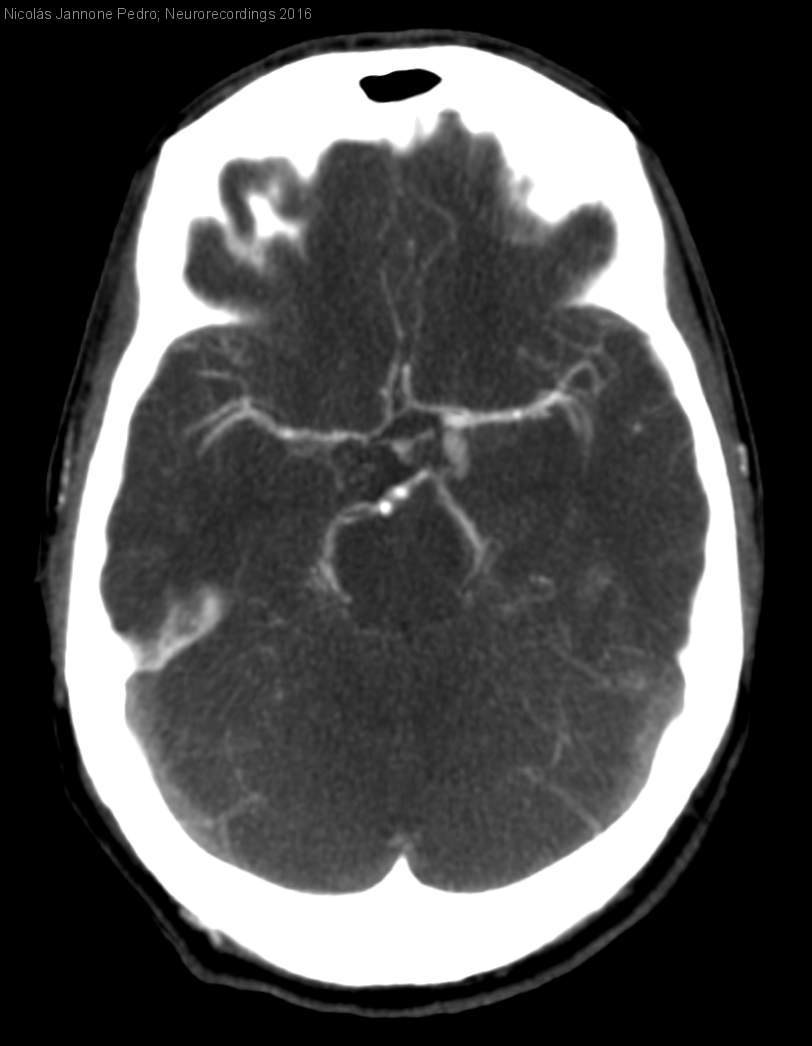

Diagnóstico final: Síndrome del seno cavernoso secundario a aneurisma de la arteria carótida interna izquierda

Varón de 30 años con antecedentes personales de migraña que hace una semana y media presenta una cefalea orbitaria izquierda de inicio brusco, distinta a las habituales. Asocia de forma progresiva diplopia binocular horizontal que...